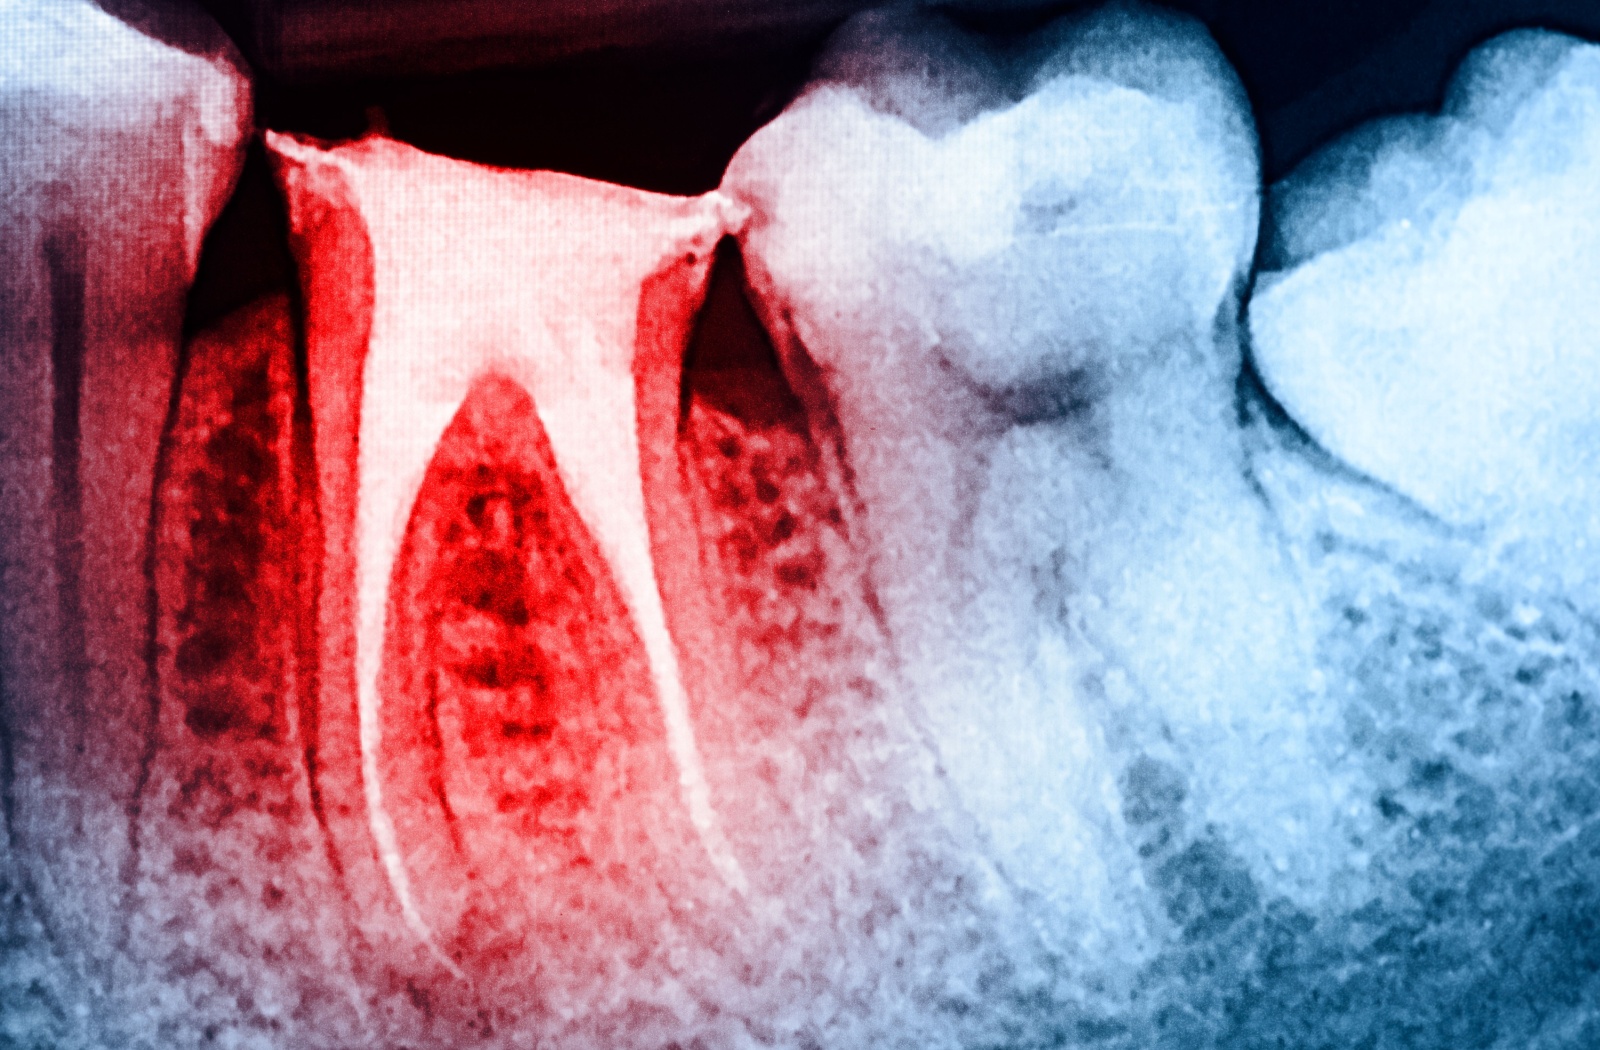

A root canal is a procedure to clean out the soft tissue inside a tooth, which can relieve pain and save it from being removed. This dental treatment addresses issues within the tooth’s interior (the pulp) to help you feel comfortable again.

- Next, they create a small opening to access the inside of the tooth and carefully clean the space.

- Once the inside of the tooth is clean, it’s filled and sealed to keep it protected.